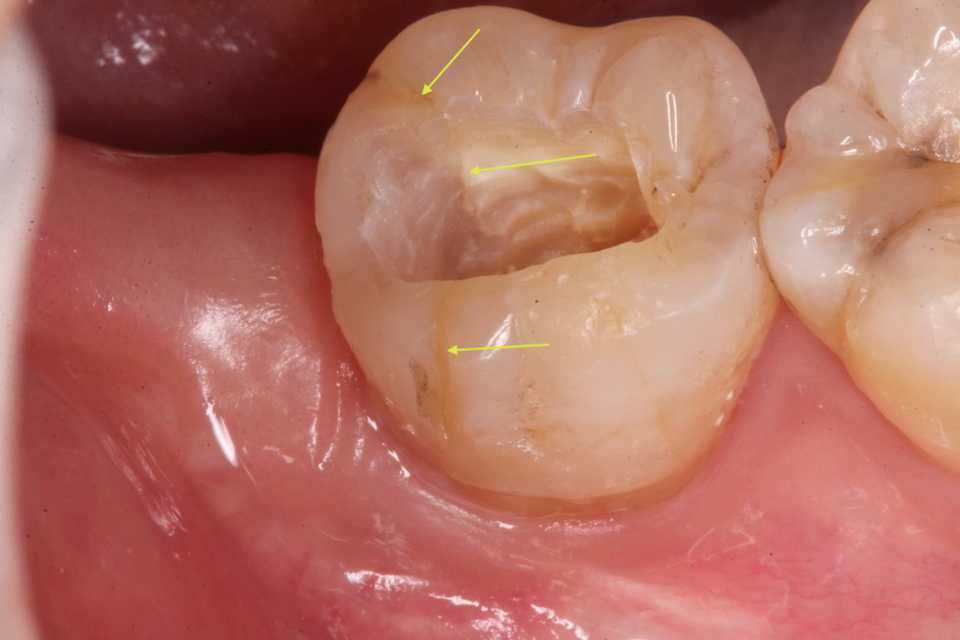

今年もお世話になりました!コロナ騒ぎ以来、年末の職場の忘年会は見合わせている。臨床系の記事はこの症例で今年は終わりになると思うが、なんとも後味の悪い内容だ。こんなことは今年で終わって欲しいものだ。40代女性、右下3、PerGAかなり歯肉が腫れており、レントゲン写真でも陰影が強く出ており広範囲な炎症があることが分かる。ちょっと心配になるほどの(蜂窩織炎=昔は死んでいた、に進展するとか)、あまり見かけない症状だった。こうなるまで放置するかな?、というか患者が歯髄を残してくれと言い張ったのかもしれない。それは現代歯科医学では不可能なのだが。見れば分かる程度のCR:ダイレクトボンディングが下手過ぎ、漏洩が起こって細菌感染していると思われるが、前医はレーザー照射でお茶を濁していた。歯科でのレーザーとはやっている感を出すためのおまじないにすぎない。僕も使ったことがあるが、全く使えない。何に使うのか分からないレベルだ。既存のCRを除去してみるとというか、ポロッと脱離した。歯髄を保存しようとは思っていないことが伝わってくる処置だった。こういうのは良くある。痛くなったら神経を取って被せるというビジネスモデルに持ち込むために地雷を仕掛けるのだ。仕込み。そこまで悪意があるのかどうかも分からないが、薄々は感じていると思う。法律用語で言うところの「未必の故意」と言っても良い。歯科業界は100年も200年も同じことをやっていて、すっかり時代遅れになっているのだが、それにどっぷり浸かり抜け出そうとは思っていない「魔境」だ。うかうか近づくと喰われてしまう。では時系列でどうぞポロッとCRが外れたが、内部は軟化象牙質だらけで、覆髄もされていない。点状露髄が認められた。この手の症例では3MIX+α-TCPがないと歯髄を保存することは難しいだろう。歯髄が少しでも残っていれば再生する可能性もあるのだ。α-TCPは入手困難になっている。そんなものが普及したら業界が食えなくなると思っている人間がいるのかもしれない。思った通りだが、歯髄は完全に失活しているように見える。根管を明示する。超音波スケーラーの#15のエンドチップで洗浄する根管内を乾燥させる必要はない。汚い綿栓を突っ込んで感染を広げるようなことをせず、根管に水平方向にエアブロウするだけで良い。一回目の3MIX+α-TCPは精製水練りだからだ。二回目の3MIX+α-TCPは50%クエン酸水練り。こうしないとすぐにはCR:ダイレクトボンディングできない。精製水練りは硬化が遅いからだ。固まったらフィニシングラインを1mm確保してCR:ダイレクトボンディングで終わり、抗生剤投与。CR:ダイレクトボンディングと言っても吟味した漏洩の心配のない製品を使う。もし治りが悪い場合は再度同じ治療をするが、どうだろうか?ちょっと心配している。